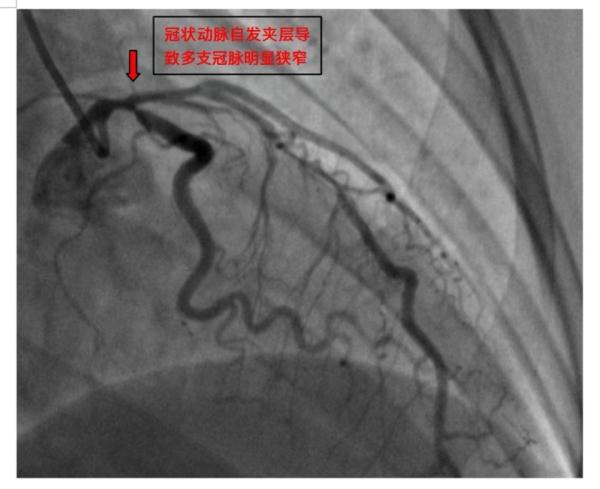

一周前,家住马王堆陶瓷城的40岁何女士晚上10时正在家看书,突然胸痛难忍,大汗淋漓,被家人送往省人民医院马王堆院区紧急就医。入院后,心电图提示,患者为急性前间壁、前壁心肌梗死。经冠脉造影检查和血管内超声检查后发现,患者冠状动脉的左主干+左前降支+回旋支出现一个自发性夹层,形成血肿,造成血管挤压狭窄达90%。如不马上处理,心脏左边将面临大面积缺血坏死,会有生命危险。

△术前